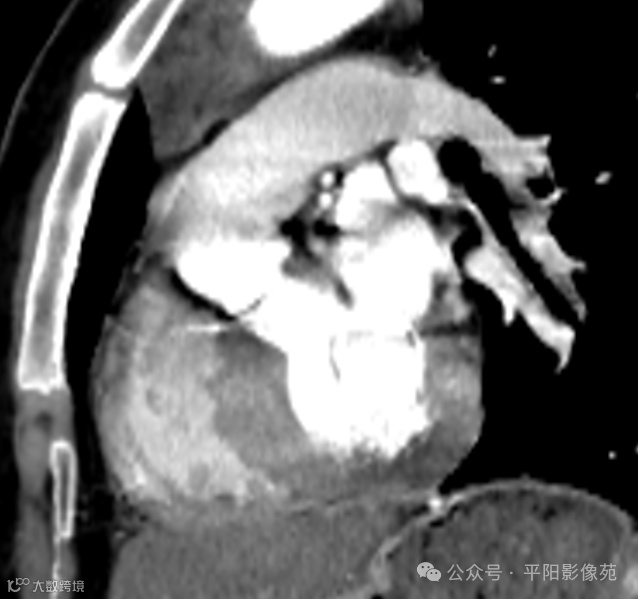

主动脉弓离断合并室间隔缺损